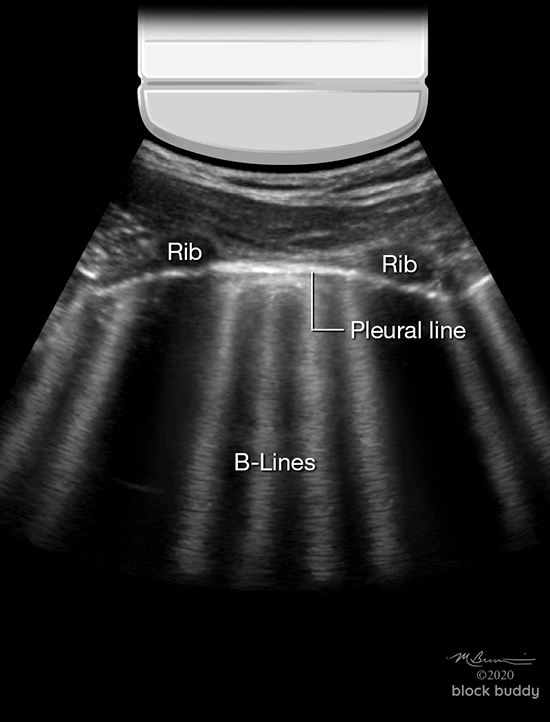

B-Lines

- Hyperechoic, vertical reverberation artifacts.

- Extend from the pleural line to the bottom of the screen.

- Obliterate A-lines.

- Move synchronously with lung sliding.

- Results from interlobular septal thickening (fluid) surrounded by air filled alveoli.

- This produces a significant acoustic impedance gradient, resulting in the reverberation artifacts.

- Most commonly seen in pulmonary edema (cardiogenic and non-cardiogenic).

- Also seen with interstitial pneumonia, acute respiratory distress syndrome (ARDS), pulmonary fibrosis, pulmonary contusion, atelectasis and malignancy.

- 2 or less B-lines between 2 ribs in any zone are a normal finding.

- 3 or more B-lines between ribs in any zone are pathologic.

- The presence of B-lines can be used to identify interstitial syndrome, but cannot distinguish between pulmonary edema, ARDS, or fibrosis.

- B-lines with lung sliding are indicative of pulmonary edema.

- B-lines without lung sliding, may indicate ARDS or pneumonia.